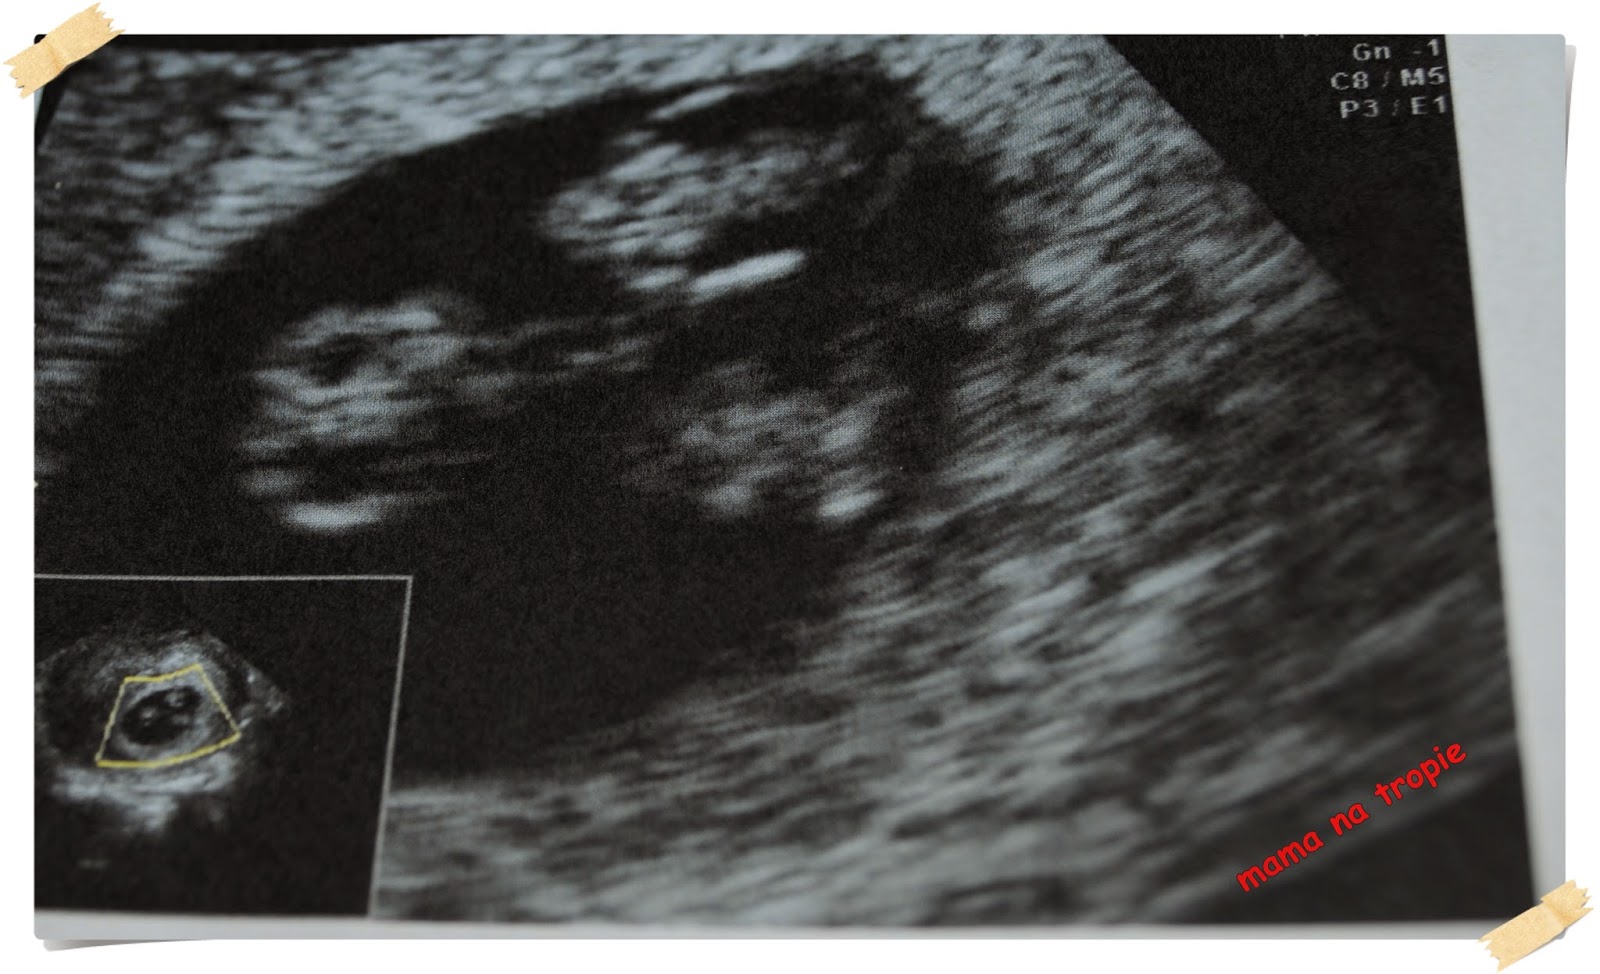

A na koniec prezent dla Was, znalazłam ostatnio pierwsze usg robione w 7 tygodniu. Tak oto wyglądają bliźniaki jednojajowe na prawie samym początku swojego rozwoju – to te dwie kuleczki, a to pośrodku wspólne to pęcherzyki żółciowe każdego z malców:)

7 tydzień ciąży bliźniaczej